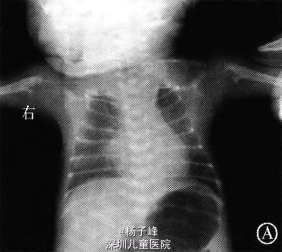

全身骨骼x线:颅骨大部分缺如;胸廓呈无力状,肋骨较细,右侧锁骨缺如;四肢诸骨形态异常,双侧肱骨近端不规整,股骨、胫骨、腓骨干骺端呈叉状改变,骨盆变小,结构异常,局部骨皮质显示模糊(图1)。血常规:WBC 18.9 X 10’/L,生化:TBil257.0 lamol/L(人院第2天),Ca 2.35 mmol/L,GLU2.03 mmol/L,余正常,甲状腺功能正常。